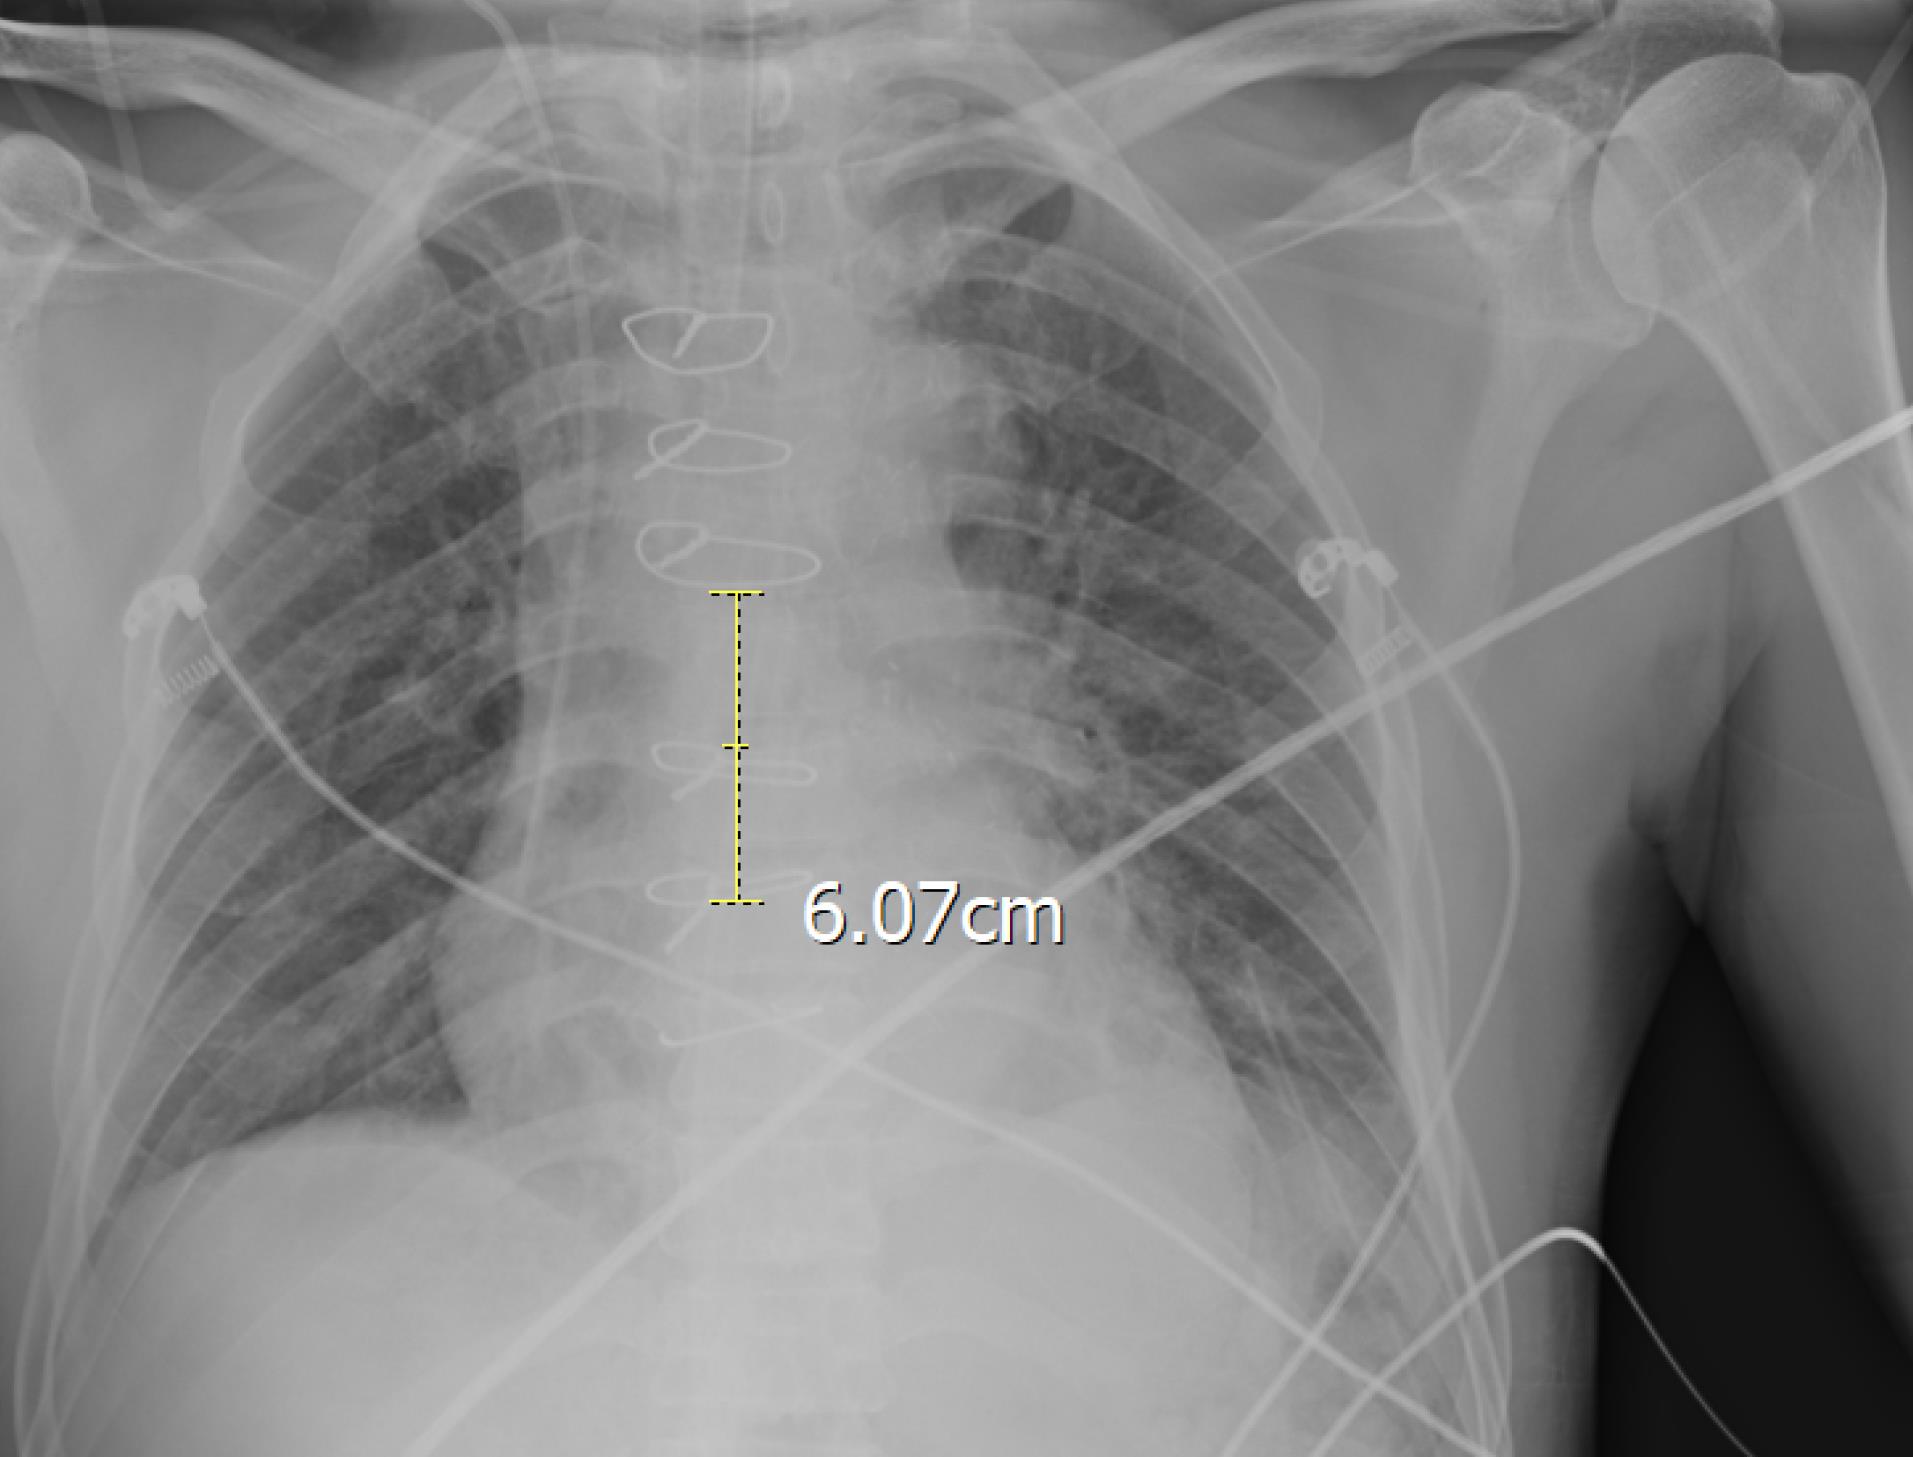

After preliminary checks, demographic data including Age, gender, weight (kg), height (cm), and body mass index (BMI) (kg/m2) were gathered. All 100 CVC were inserted in the internal jugular vein with disinfection method with alcoholic chlorhexidine antiseptic for skin preparation, then cvc was fixed according to the Press formula by a cardiac anesthesiologist in the operating room (OR). According to Peres’ formula, the depth of CVC insertion should be height/10 cm for the right internal jugular vein (IJV), after fixation Chest radiography was performed for patients in the supine position, and the tip position of the catheter was assessed according to the distance between the CVC tip and the carina. We measured the distance between the carina and CVC and recorded it as a Distance variable. One centimeter distance from the carina (higher and lower) is the proper CVC tip position, and other patients were in the wrong CVC tip position and cvc was fixed in correct depth. All of the study demographic and variables related to surgery accompanied by the result of chest radiography were gathered and inserted into the patient list. Figure 1 shows the chest radiography of one patient with incorrect CVC tip insertion. Figure 2 landmarked the proper position of CVC tips according to the carina location on the chest radiography. Figure 3 shows the Bland Altman plot for the Peres estimation and the actual place. The x-axis represents the mean of the Peres estimation and the actual place, while the y-axis shows the difference between the two. The plot includes a red line indicating the mean difference (or bias) between the estimations and actual values, with the blue lines representing the 95% limits of agreement (mean difference ± 1.96 standard deviations). Each point represents an individual data pair, illustrating the variability between the estimation and actual place across different values. This plot is used to assess the agreement between the two methods.

Figure 1.

chest radiography of study patients with incorrect CVC tip insertion according to Peres formula

landmarking of correct CVC tip location according to carina in patient with incorrect CVC tip position according to Peres formula